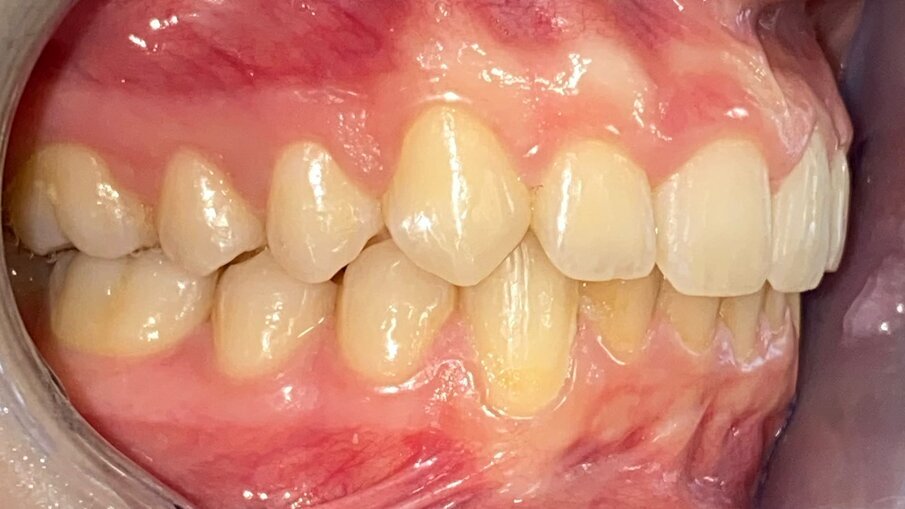

All’esame obiettivo intraorale si riscontra sul piano frontale un severo morso profondo con precontatto traumatico degli incisivi superiori contro la papilla retroincisiva e le rughe palatine anteriori durante la massima intercuspidazione, con overbite di 10 mm (Fig. 5). Dalle foto laterali si evidenzia una malocclusione di Classe II divisione 2 con scissor bite dell’elemento 1.5 (Figg. 6, 7), mentre dalle foto occlusali si rileva un grave affollamento con contrazione di entrambe le arcate maggiore nella zona premolare (Figg. 8, 9). L’analisi di Bolton mostra un eccesso superiore 3-3 di 2,34 mm (73,6%) e 6-6 di 2,76 mm (88,8%). L’analisi cefalometrica evidenzia una Classe II scheletrica, modello facciale normodivergente, angolo interincisale aumentato, incisivi superiori e inferiori retroinclinati (Fig. 10). La radiografia panoramica mostra la presenza dei germi dei terzi molari, assenza di parallelismo tra le radici dei premolari inferiori (Fig. 11) e una sovraeruzione degli incisivi inferiori che crea un doppio piano tra gli incisivi e i molari, segno di una curva di Spee molto profonda.

Fig. 6_Laterale destra pre-trattamento.

Fig. 7_Laterale sinistra pre-trattamento.